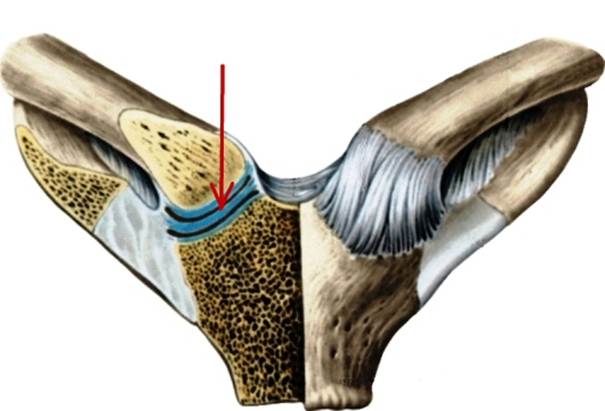

S: Стрелка указывает на art. Costotransversaria

S: Стрелка указывает на art. Capitis costae

S: Стрелками выделен art…